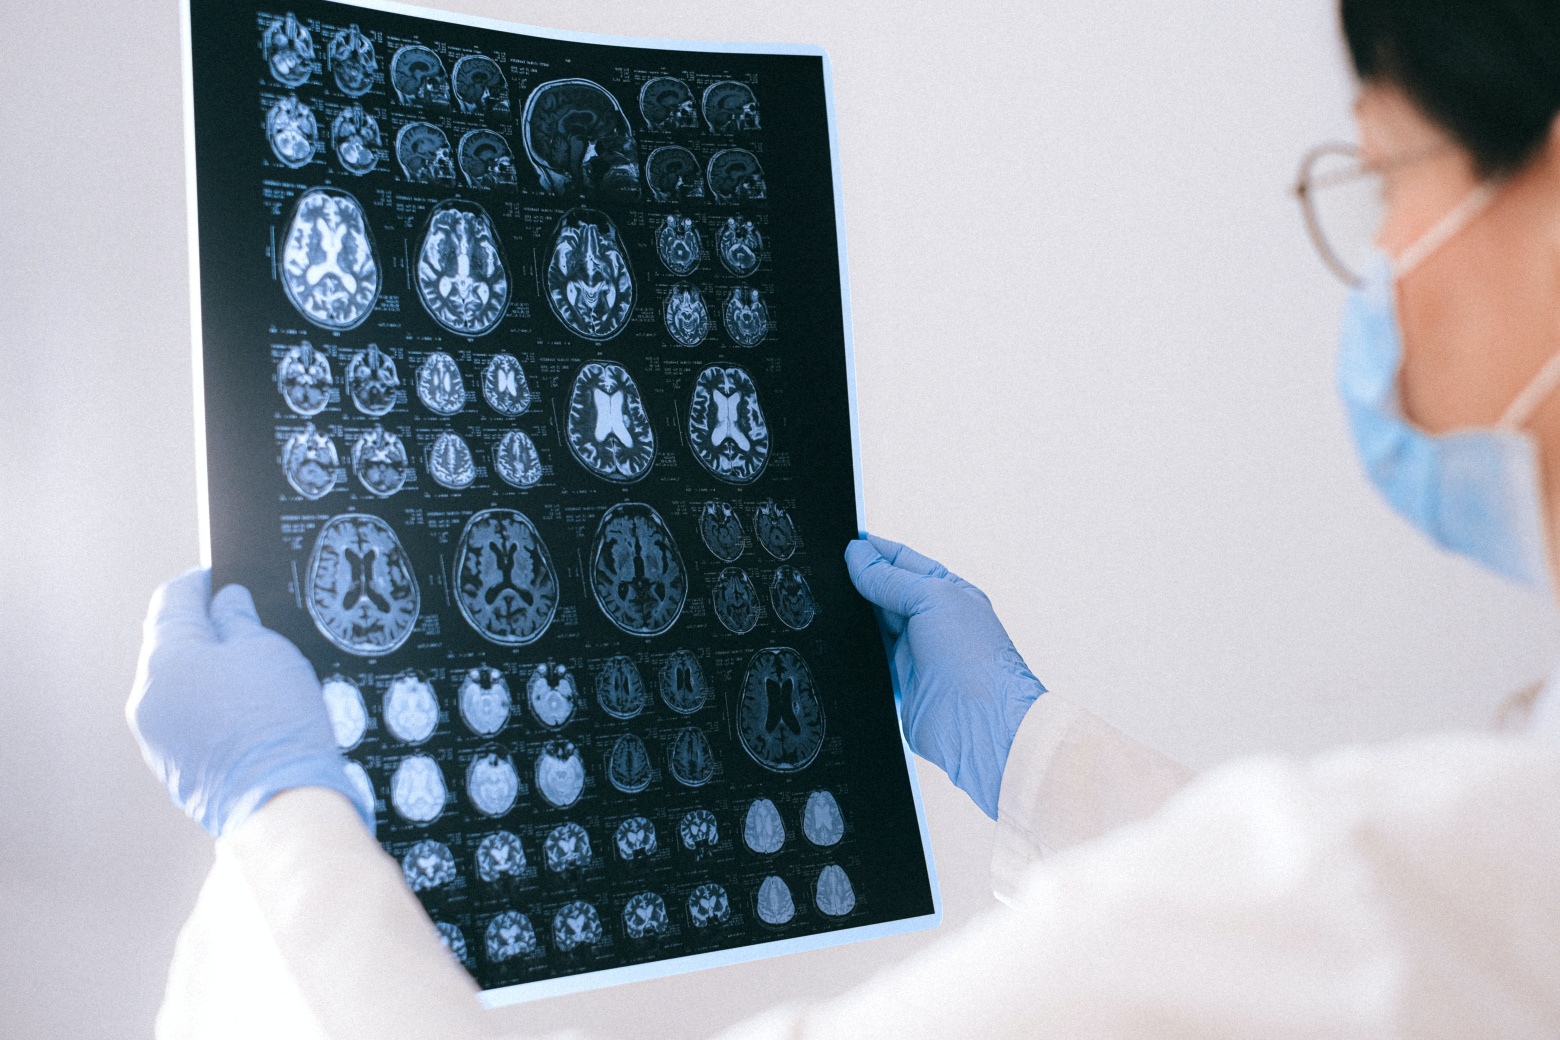

사람들은 일반적으로 뇌출혈에 비해 치료를 받을 수 있는 시간이 길다고 생각하지만 한 번 뇌혈관이 막히면 뇌세포가 죽기 시작하므로 3시간 이내에 혈전용해제를 맞거나 뇌세포 괴사를 예방하는 시술을 받는 것이 중요합니다.